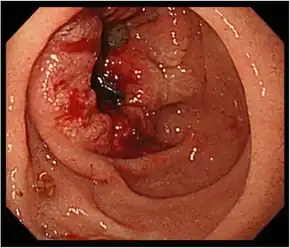

| Endoscopic image of adenocarcinoma of duodenum seen in the post-bulbar duodenum | |

Duodenal cancer is a cancer in the first section of the small intestine known as the duodenum. Cancer of the duodenum is relatively rare compared to stomach cancer and colorectal cancer. Its histology is usually adenocarcinoma.

In terms of the evaluation of the duodenum, fiberoptic endoscopy has replaced barium studies for a better diagnosis.[2]